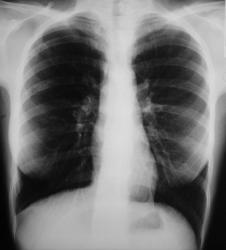

При расшифровке профилактических цифровых флюорограмм, пациент "взят на контроль".

Произведено стандартное исследование в прямой и правой боковой проекциях. Справа на уровне 4 ребра дифференцируется дополнительная крупноочаговая тень размерами 1,3 х 1,8 см.